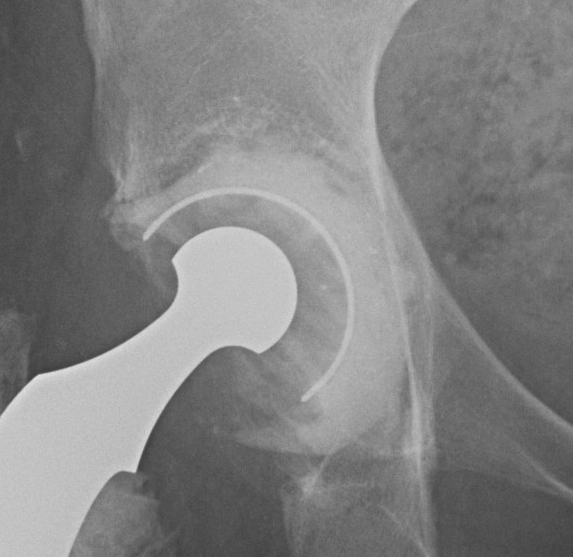

3. Trabecular metal components

New material made of element tantalum

1. Interconnecting porous material

- 80% porous

- allows 2-3 X bony ingrowth

2. Less stiff

- improved remodelling of BG underneath

3. High cancellous bone coefficient of friction

- excellent initial stability

- may need less than traditional 50% host bone contact

- may not need screws

Ream host bone for press fit cut

- trial then secure trabecular augment with screws

- press fit cup with cement between augment and cup

- screw augmentation of cup